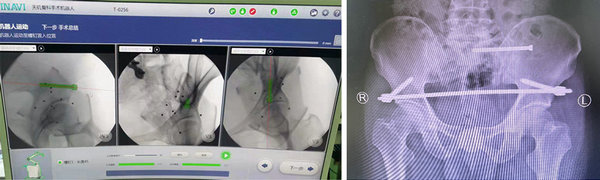

创伤骨科任海东主任带领手术团队通过术前的严密规划设计,借助新引进的骨盆专用手术床、骨盆微创复位系统及天玑骨科机器人为患者进行了“骨盆骨折天玑机器人导航下复位内固定术”,通过专用C型臂透视下取得骨盆图像,在电脑上规划螺钉方向。

在天玑骨科机器人导航下精准定位,使用骨盆前环infix内固定架固定,透视见位置及长短适中,再次行C型臂透视正侧位见骨折对位对线良好,螺钉位置以及长短均适中,通过三个不到3厘米的小创口,顺利完成手术。